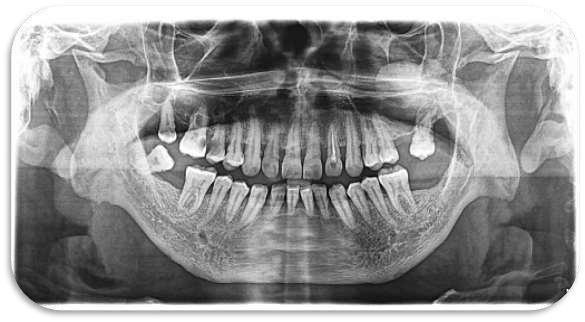

La ortopantomografía revela:

Dos supernumerarios de morfología cónica en la región interincisal superior

Ambos mesiodens erupcionados, en coexistencia con los incisivos centrales permanentes.

Ausencia de patología periapical o lesiones radiolúcidas asociadas

Pieza 2.1 y 1.1. 2.2 1.2 con mesioversion

Presencia germen dentario piezas 8

Doble mesiodens erupcionado en región anterosuperior, coexistiendo con incisivos centrales permanentes erupcionados y sin diastema.